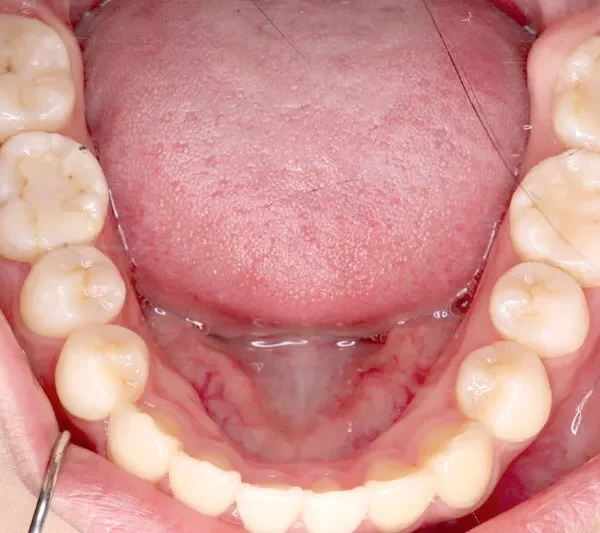

• 初診

初診